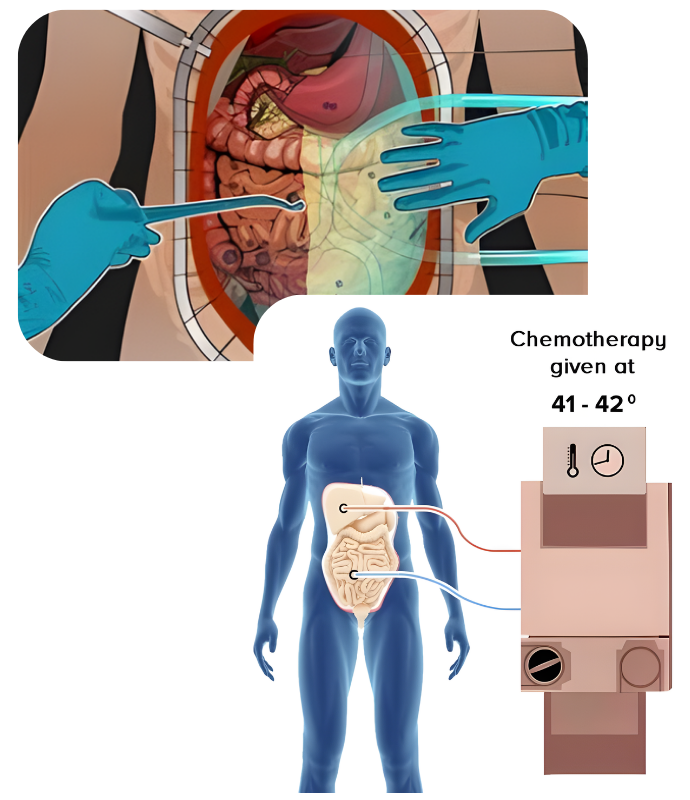

HIPEC is performed in a single operative session under general anesthesia and involves two integrated treatment phases.

Cytoreductive Surgery (CRS)

Removal of all visible tumor deposits from the abdominal cavity

May include resection of affected organs or peritoneal surfaces

Objective is to achieve minimal or no visible residual disease

The success of HIPEC largely depends on the completeness of tumor removal during this stage.

Heated Chemotherapy Circulation

Chemotherapy solution heated to 41–43°C

Circulated within the abdomen for 60–90 minutes

Continuous movement ensures uniform drug distribution

Heat enhances chemotherapy effectiveness by damaging cancer cells and increasing drug penetration.

Targeted Local Therapy Advantage

High local drug concentration at tumor sites

Limited systemic absorption and toxicity

Improved effectiveness against microscopic residual disease